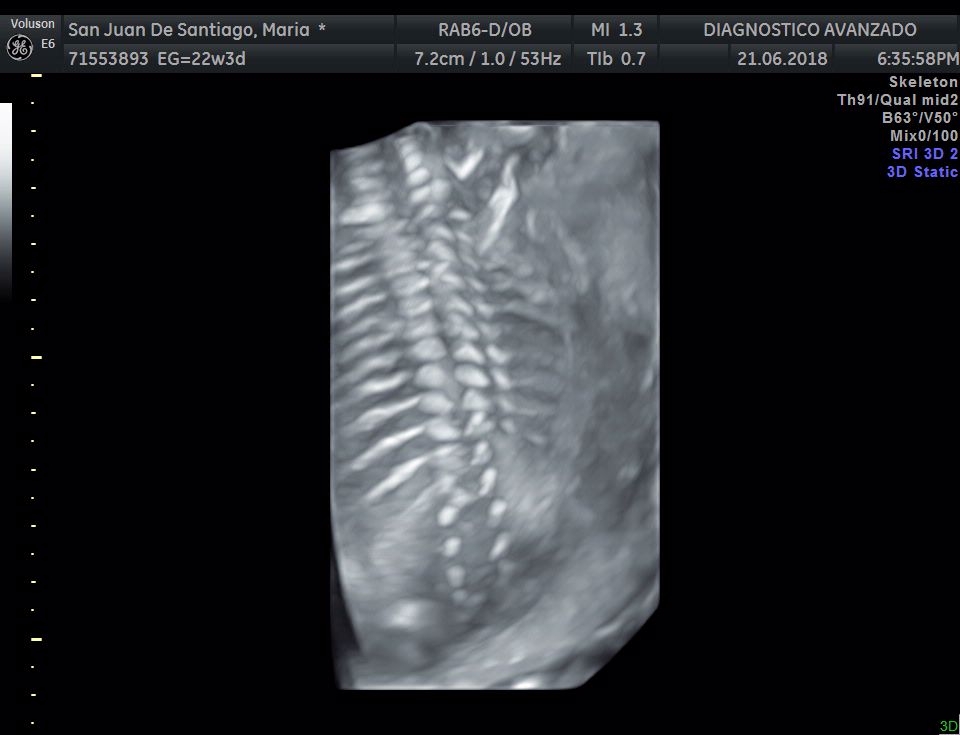

¡Hola a todos! Hoy hemos ido a hacer la tradicional ecografía 3D de la niña, os dejamos todo el material (aunque es un poco demasiado).